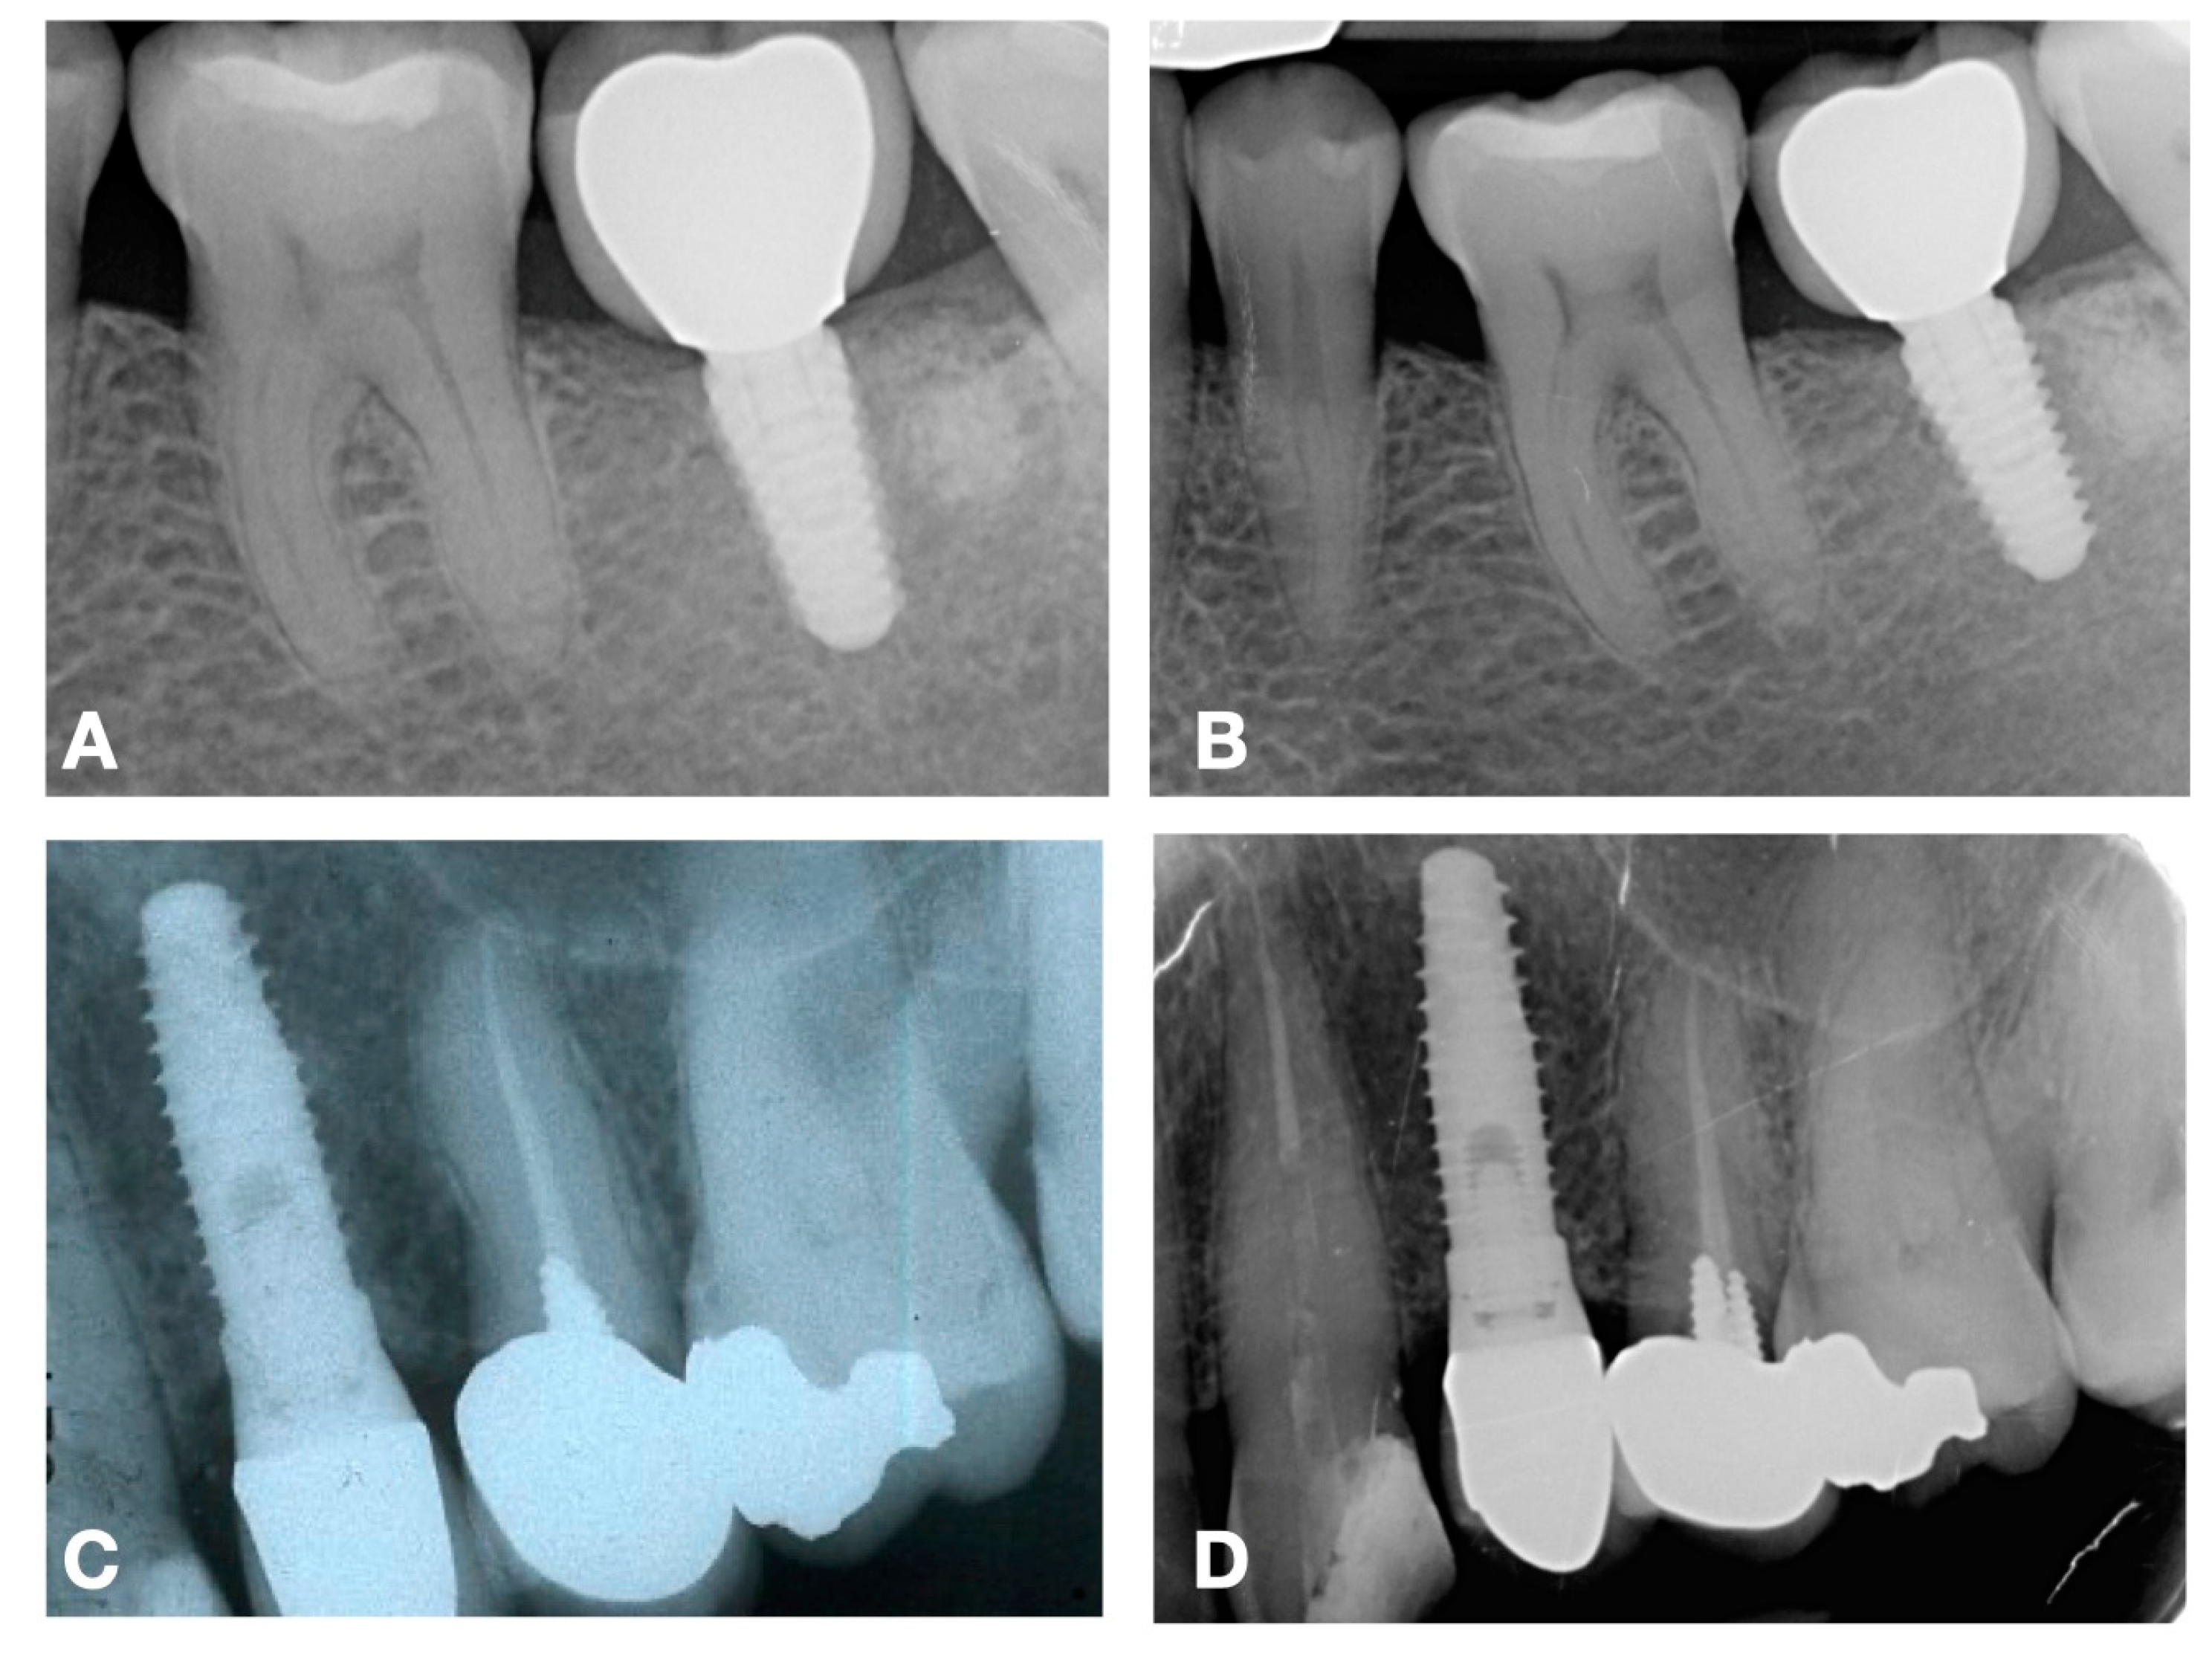

2. Features of Different Prosthetic Emergence Profiles

3. Assessing Marginal Bone Level

5. Implications for Clinicians

6. Evidence from the Literature